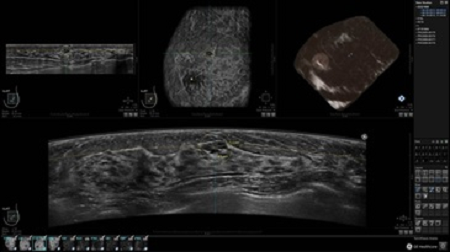

• Получение объемных 3D изображений с возможностью покадрового просмотра

• Алгоритмы обработки изображений: алгоритм однородности изображения ткани (TEA), подавление зернистости, компенсация акустической тени от соска (NSC), определение границ молочной железы (BBD), определение стенки грудной клетки

• Получение изображений в поперечной плоскости (в реальном времени) и в коронарной плоскости (статическая, для указания нахождения соска)

• Отображение объемных 3D ультразвуковых изображений, которые состоят из традиционных поперечных и воссозданных коронарных и сагиттальных проекций

• Многооконный просмотр: 4 - 12 изображений

• Стандартизованная ориентация изображения: «толстый срез» в коронарной плоскости; поперечная; сагиттальная плоскость; радиальный и антирадиальный поворот изображения; просмотр исключительно области интереса

• Изменяемая толщина среза: 0,5 - 10,0 мм (шаг 0,5 мм)

• Срез: 0,5 - 2,0 мм (шаг 0,5 мм)

• 360 ° APC - отображение области по «любой точке компаса»

• Одновременный просмотр двух изображений для сопоставления в коронарной плоскости